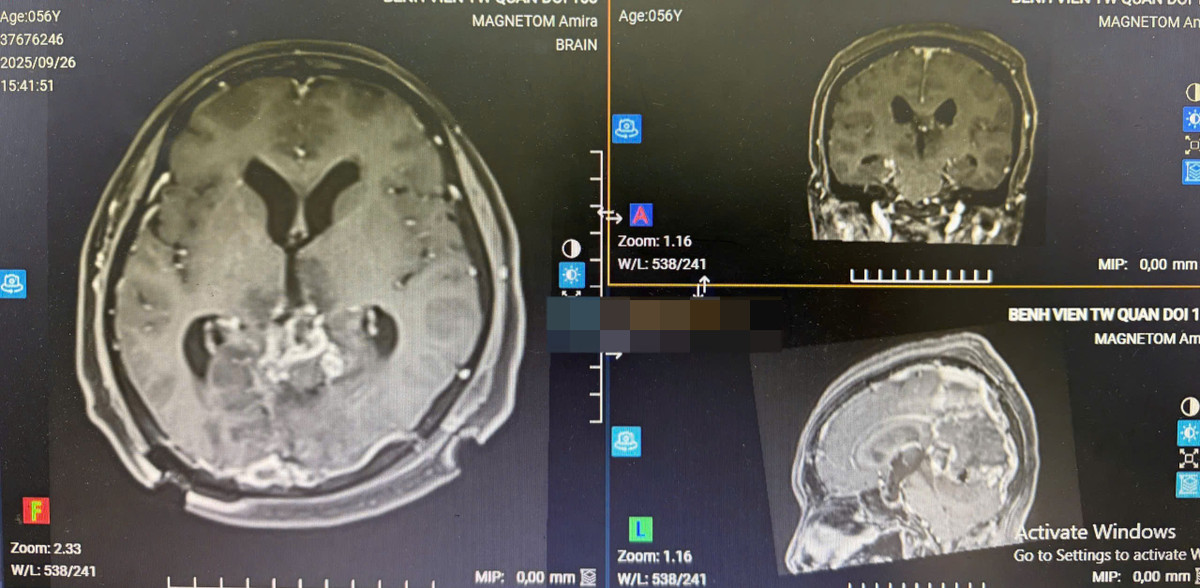

Gần đây, Bệnh viện Trung ương Quân đội 108 đã tiếp nhận một bệnh nhân nữ, 56 tuổi với khối u màng não rất lớn, vùng liềm, lều tiểu não, chèn ép sâu trong nhu mô não.

Bệnh nhân nhập viện trong tình trạng đau đầu, giảm thị lực. Kích thước khối u lớn (gần 8cm), tăng sinh mạch và vị trí phức tạp, tiềm ẩn nhiều rủi ro như mất máu, ảnh hưởng thị lực.

Phim chụp CT trước phẫu thuật - Ảnh BVCC

Phim chụp CT sau mổ - Ảnh BVCC